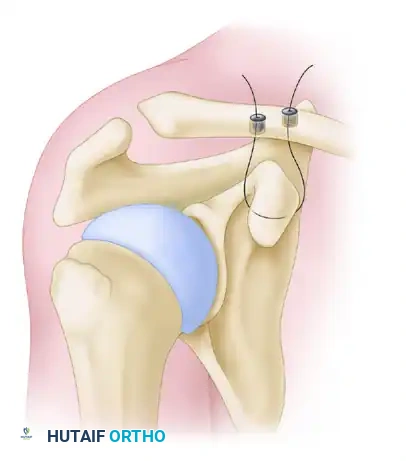

5. Clavicular Tunnel Placement

Accurate tunnel placement is the most critical step in recreating the native anatomy.

* Conoid Tunnel (Posterior/Medial): Drill the first tunnel 45 mm medial to the native distal clavicular articular surface. Note: If a 10 mm distal clavicular resection has already been performed, this tunnel should be placed 35 mm from the new cut edge. Position this tunnel slightly posterior on the clavicle to recreate the native conoid insertion.

* Trapezoid Tunnel (Anterior/Lateral): Drill the second tunnel 15 mm lateral to the conoid tunnel. Position this tunnel slightly anteriorly to recreate the native trapezoid insertion.

* Use an appropriate cannulated reamer (typically 5.0 mm to 6.0 mm, depending on graft diameter) over a guide pin.

Mazzocca anatomic coracoclavicular reconstruction: Incision and precise tunnel placement. The posterior tunnel recreates the conoid ligament, while the anterior tunnel recreates the trapezoid ligament.